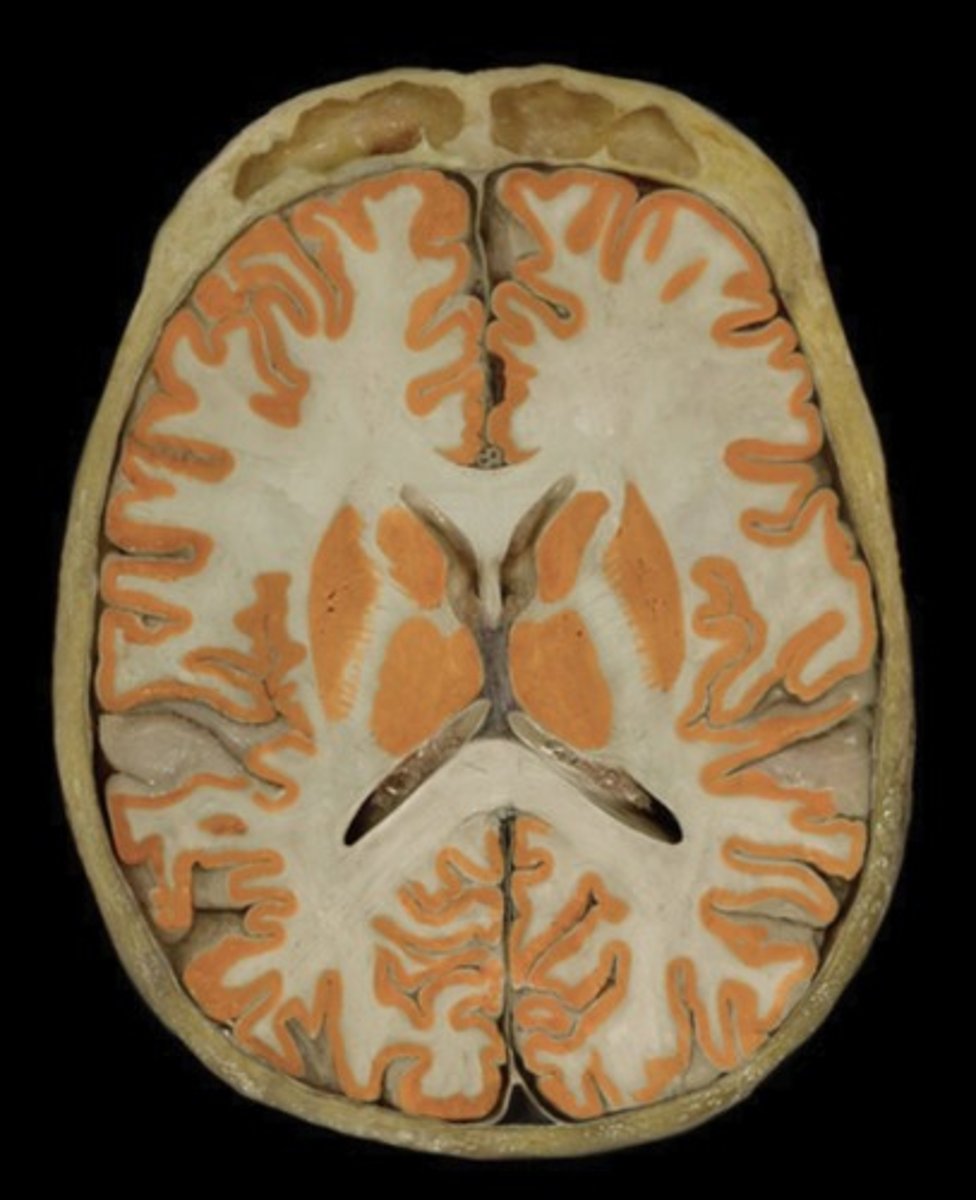

Gray matter

Name this structure

Occipital Lobe (transverse section)

Name this structure

Temporal Lobe (transverse section)

Name this structure